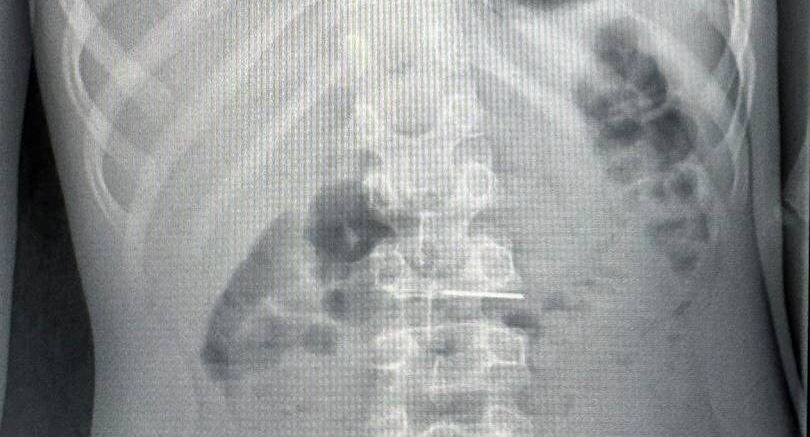

Мальчика привезли в больницу с жалобами на боль в живот. Ему провели рентгеноскопию брюшной полости, во время которой специалисты заметили острый предмет в верхних отделах желудочно-кишечного тракта.

«Во время гастроскопии, проведенной в условиях операционной, мы обнаружили, что игла зафиксировалась острым концом в слизистой оболочке двенадцатиперстной кишки. Для удаления иглы мы использовали биопсийные щипцы, с помощью которых аккуратно извлекли инородное тело из слизистой оболочки и затем переместили его в желудок, чтобы избежать повреждения окружающих тканей», — подчеркнула врач-эндоскопист Зоя Голикова.

Зетем инородное тело захватили специальным инструментом и полностью извлекли. Вмешательство длилось полчаса. Мальчика выписали уже на следующий день.